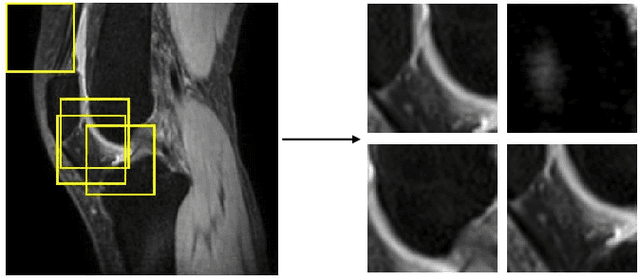

Abstract:Two-dimensional (2D) fast spin echo (FSE) techniques play a central role in the clinical magnetic resonance imaging (MRI) of knee joints. Moreover, three-dimensional (3D) FSE provides high-isotropic-resolution magnetic resonance (MR) images of knee joints, but it has a reduced signal-to-noise ratio compared to 2D FSE. Deep-learning denoising methods are a promising approach for denoising MR images, but they are often trained using synthetic noise due to challenges in obtaining true noise distributions for MR images. In this study, inherent true noise information from 2-NEX acquisition was used to develop a deep-learning model based on residual learning of convolutional neural network (CNN), and this model was used to suppress the noise in 3D FSE MR images of knee joints. The proposed CNN used two-step residual learning over parallel transporting and residual blocks and was designed to comprehensively learn real noise features from 2-NEX training data. The results of an ablation study validated the network design. The new method achieved improved denoising performance of 3D FSE knee MR images compared with current state-of-the-art methods, based on the peak signal-to-noise ratio and structural similarity index measure. The improved image quality after denoising using the new method was verified by radiological evaluation. A deep CNN using the inherent spatial-varying noise information in 2-NEX acquisitions was developed. This method showed promise for clinical MRI assessments of the knee, and has potential applications for the assessment of other anatomical structures.